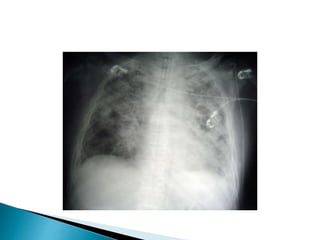

X RAY

 The radiological studies show consolidation

with the basal predominance.

HRCT:

 Area of air space consolidation

 Ground glass opacities

 Broncial wall thickening and,dilation

Typical imaging pattern of organising pneumonia with patchy alveolar opacities on chest

radiograph.

Copyright © BMJ Publishing Group Ltd & British Thoracic Society. All rights reserved.